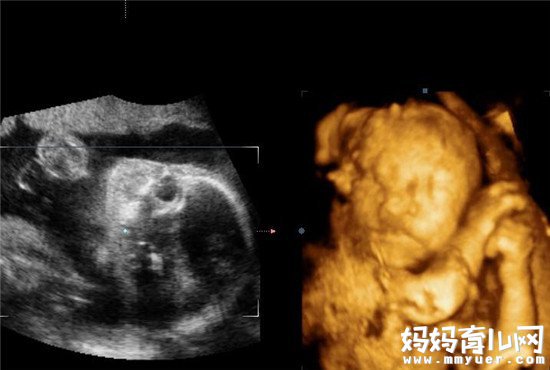

说到孕检项目,四维彩超必须得是重磅戏啊!四维彩超是用来排查胎儿畸形的,在怀孕20多周的时候做最准确,由于二胎开放后,现在孕妇特别多,所以做四维彩超也是要提前和医生预约的,做彩超前没有什么特别的注意事项,别紧张就行了。

一般每个孕妇做四维彩超的时间在20分钟左右,医生会全面地检查胎儿,最后给出一张四维彩超报告单。单子上有宝宝的图片,也算是第一次目睹宝宝的容貌了吧,还有其他胎儿发育的数据。据说就凭一张报告单就能看出男女,怎么看呢?

四维彩超看男女怎么看

四维彩超怎么看男女